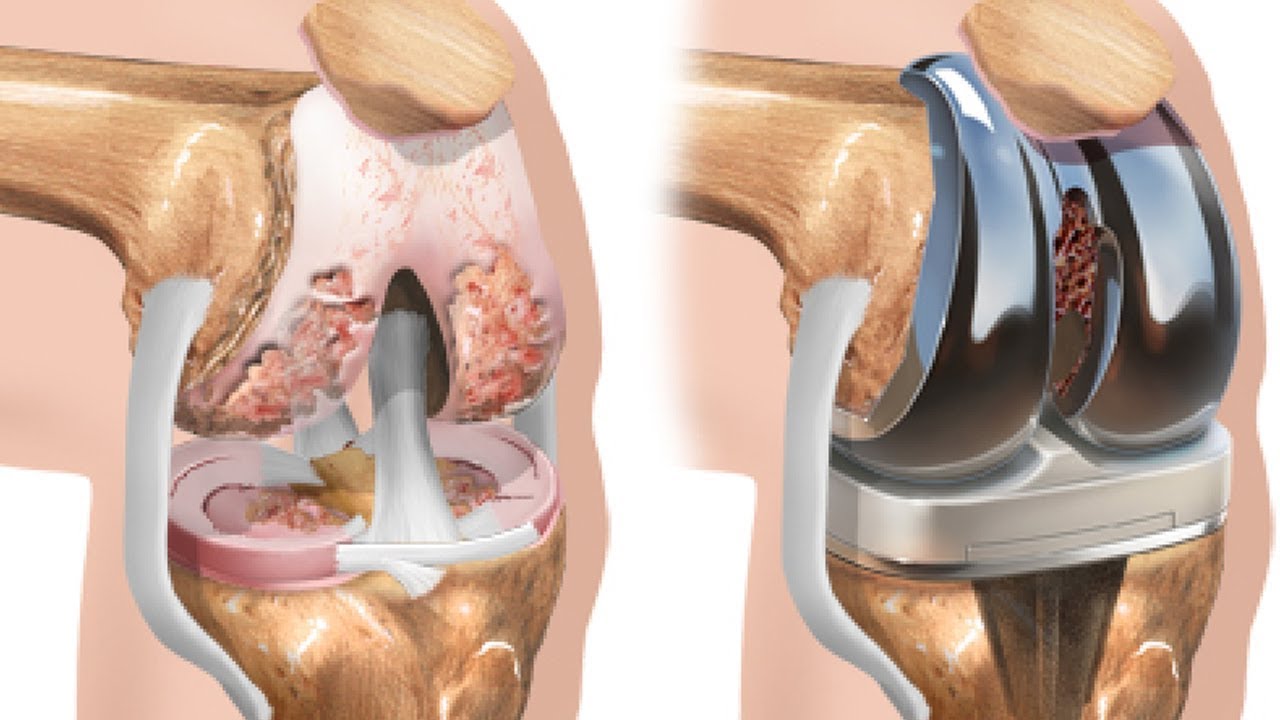

Остеоартроз является хроническим заболеванием суставов, в основе которого лежит дистрофическое изменение хрящевых тканей с их последующим разрушением и возникновением характерных деформаций. Хрящ истончается, становится шероховатым, растрескивается, теряет прочность и эластичность. В результате этого патологического процесса формируются краевые костные разрастания — остеофиты.

Болезнь чаще поражает крупные суставы. К специалистам обращаются пациенты, у которых диагностируется остеоартроз коленного сустава, который нередко формируется в результате бытовых и профессиональных травм. У пожилых людей на фоне остеопороза, нарушений обмена веществ и генетической предрасположенности может развиваться остеоартроз тазобедренного сустава, приводящий к инвалидизации и значительным двигательным ограничениям в будущем. Люди пенсионного возраста в группе риска по развитию опорно-двигательных нарушений. После 60 лет у большинства из них развивается остеопороз и остеоартроз кистей рук и других крупных суставов.

У 9 из 172 больных (5,2 %) отмечалось быстрое прогрессирование заболевания, что потребовало направления пациентов на хирургическое лечение – тотальное эндопротезирование тазобедренного сустава.